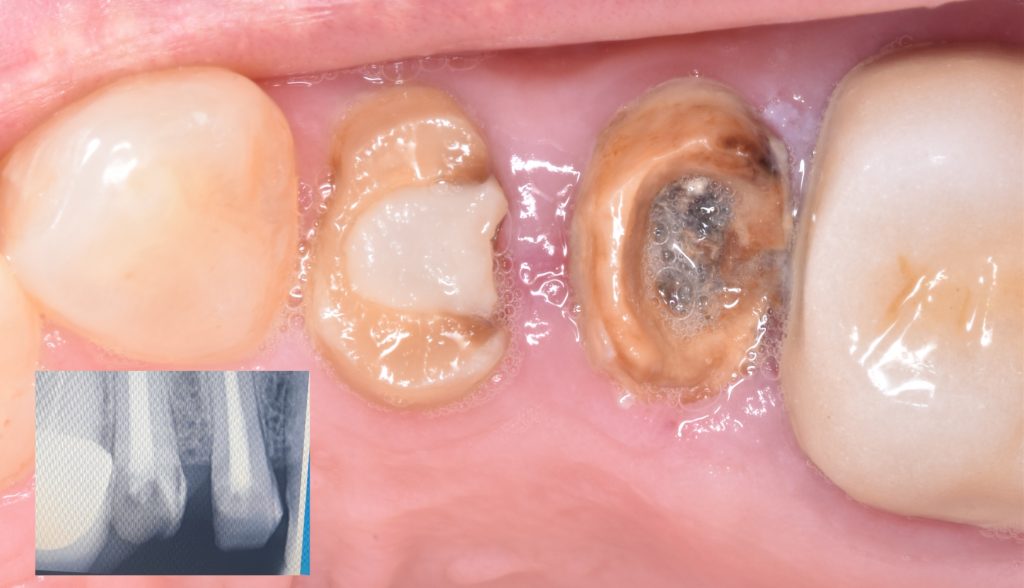

Upper right first and second premolars

Were badly decayed

Upon examination

I decided to go for indirect lithium disilicate restorations

Caries removal with aid of caries detector dye